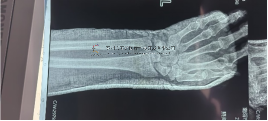

可快速通過脛骨干骨折X線正側(cè)位片識別脛骨干骨折三維模型,并出具包含骨折端位移距離、骨折旋轉(zhuǎn)角度、骨折模擬復(fù)位數(shù)據(jù)等信息的診斷報(bào)告,輔助醫(yī)師術(shù)前診斷及規(guī)劃,在識別脛骨干骨折的分型、骨折位移旋轉(zhuǎn)參數(shù)具有良好一致性,已錄用中國醫(yī)師協(xié)會骨科醫(yī)師年會電子壁報(bào)1篇。